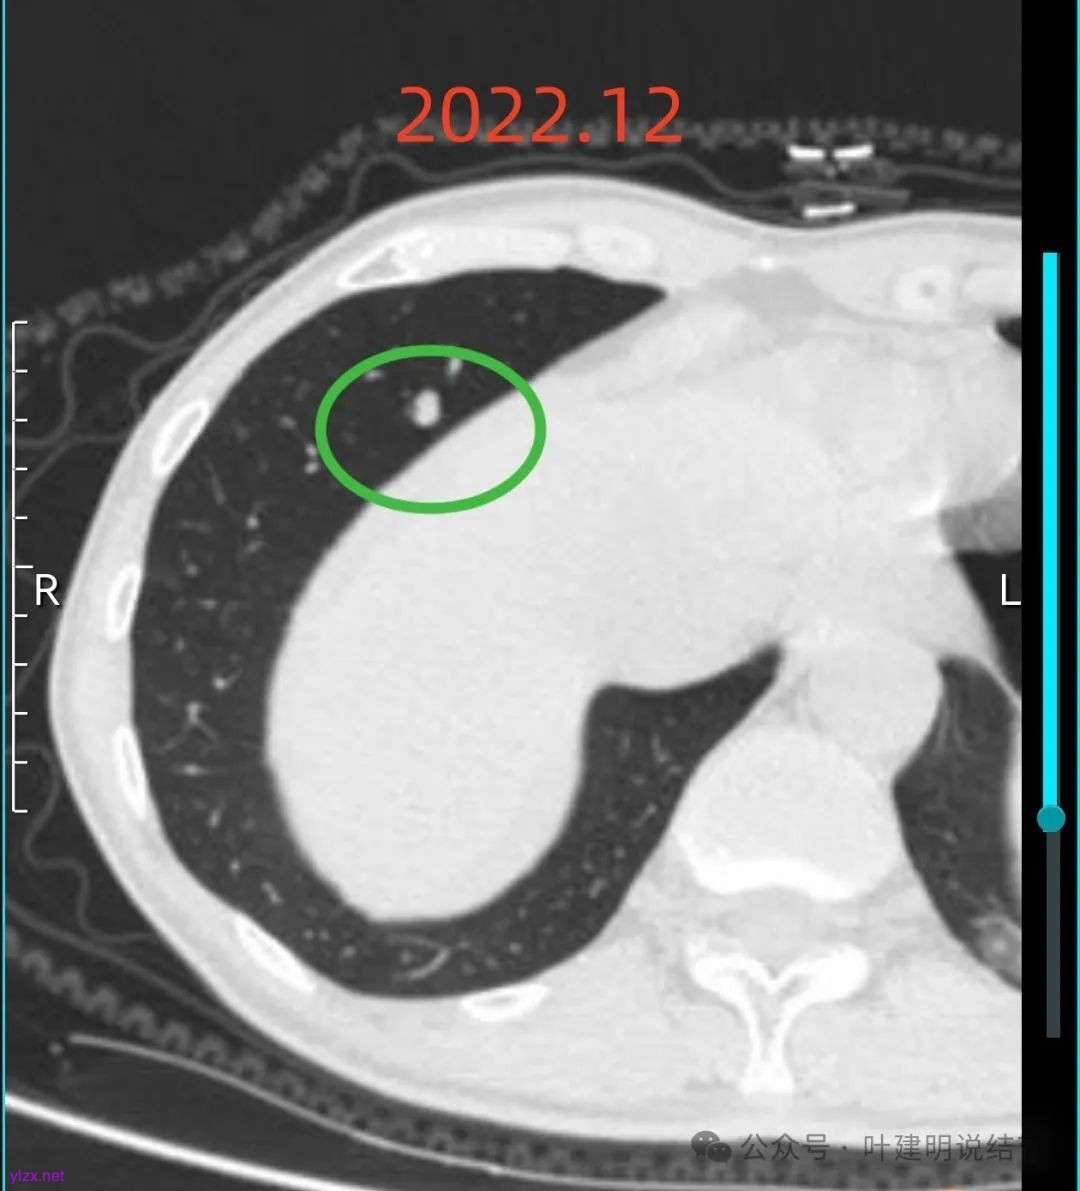

我们先来看2022年12月时的影像:

右下叶实性结节,轮廓较清,密度高,单次影像是否恶性不太好定,要随访,总体上觉得密度太高了点,不是太像恶性。